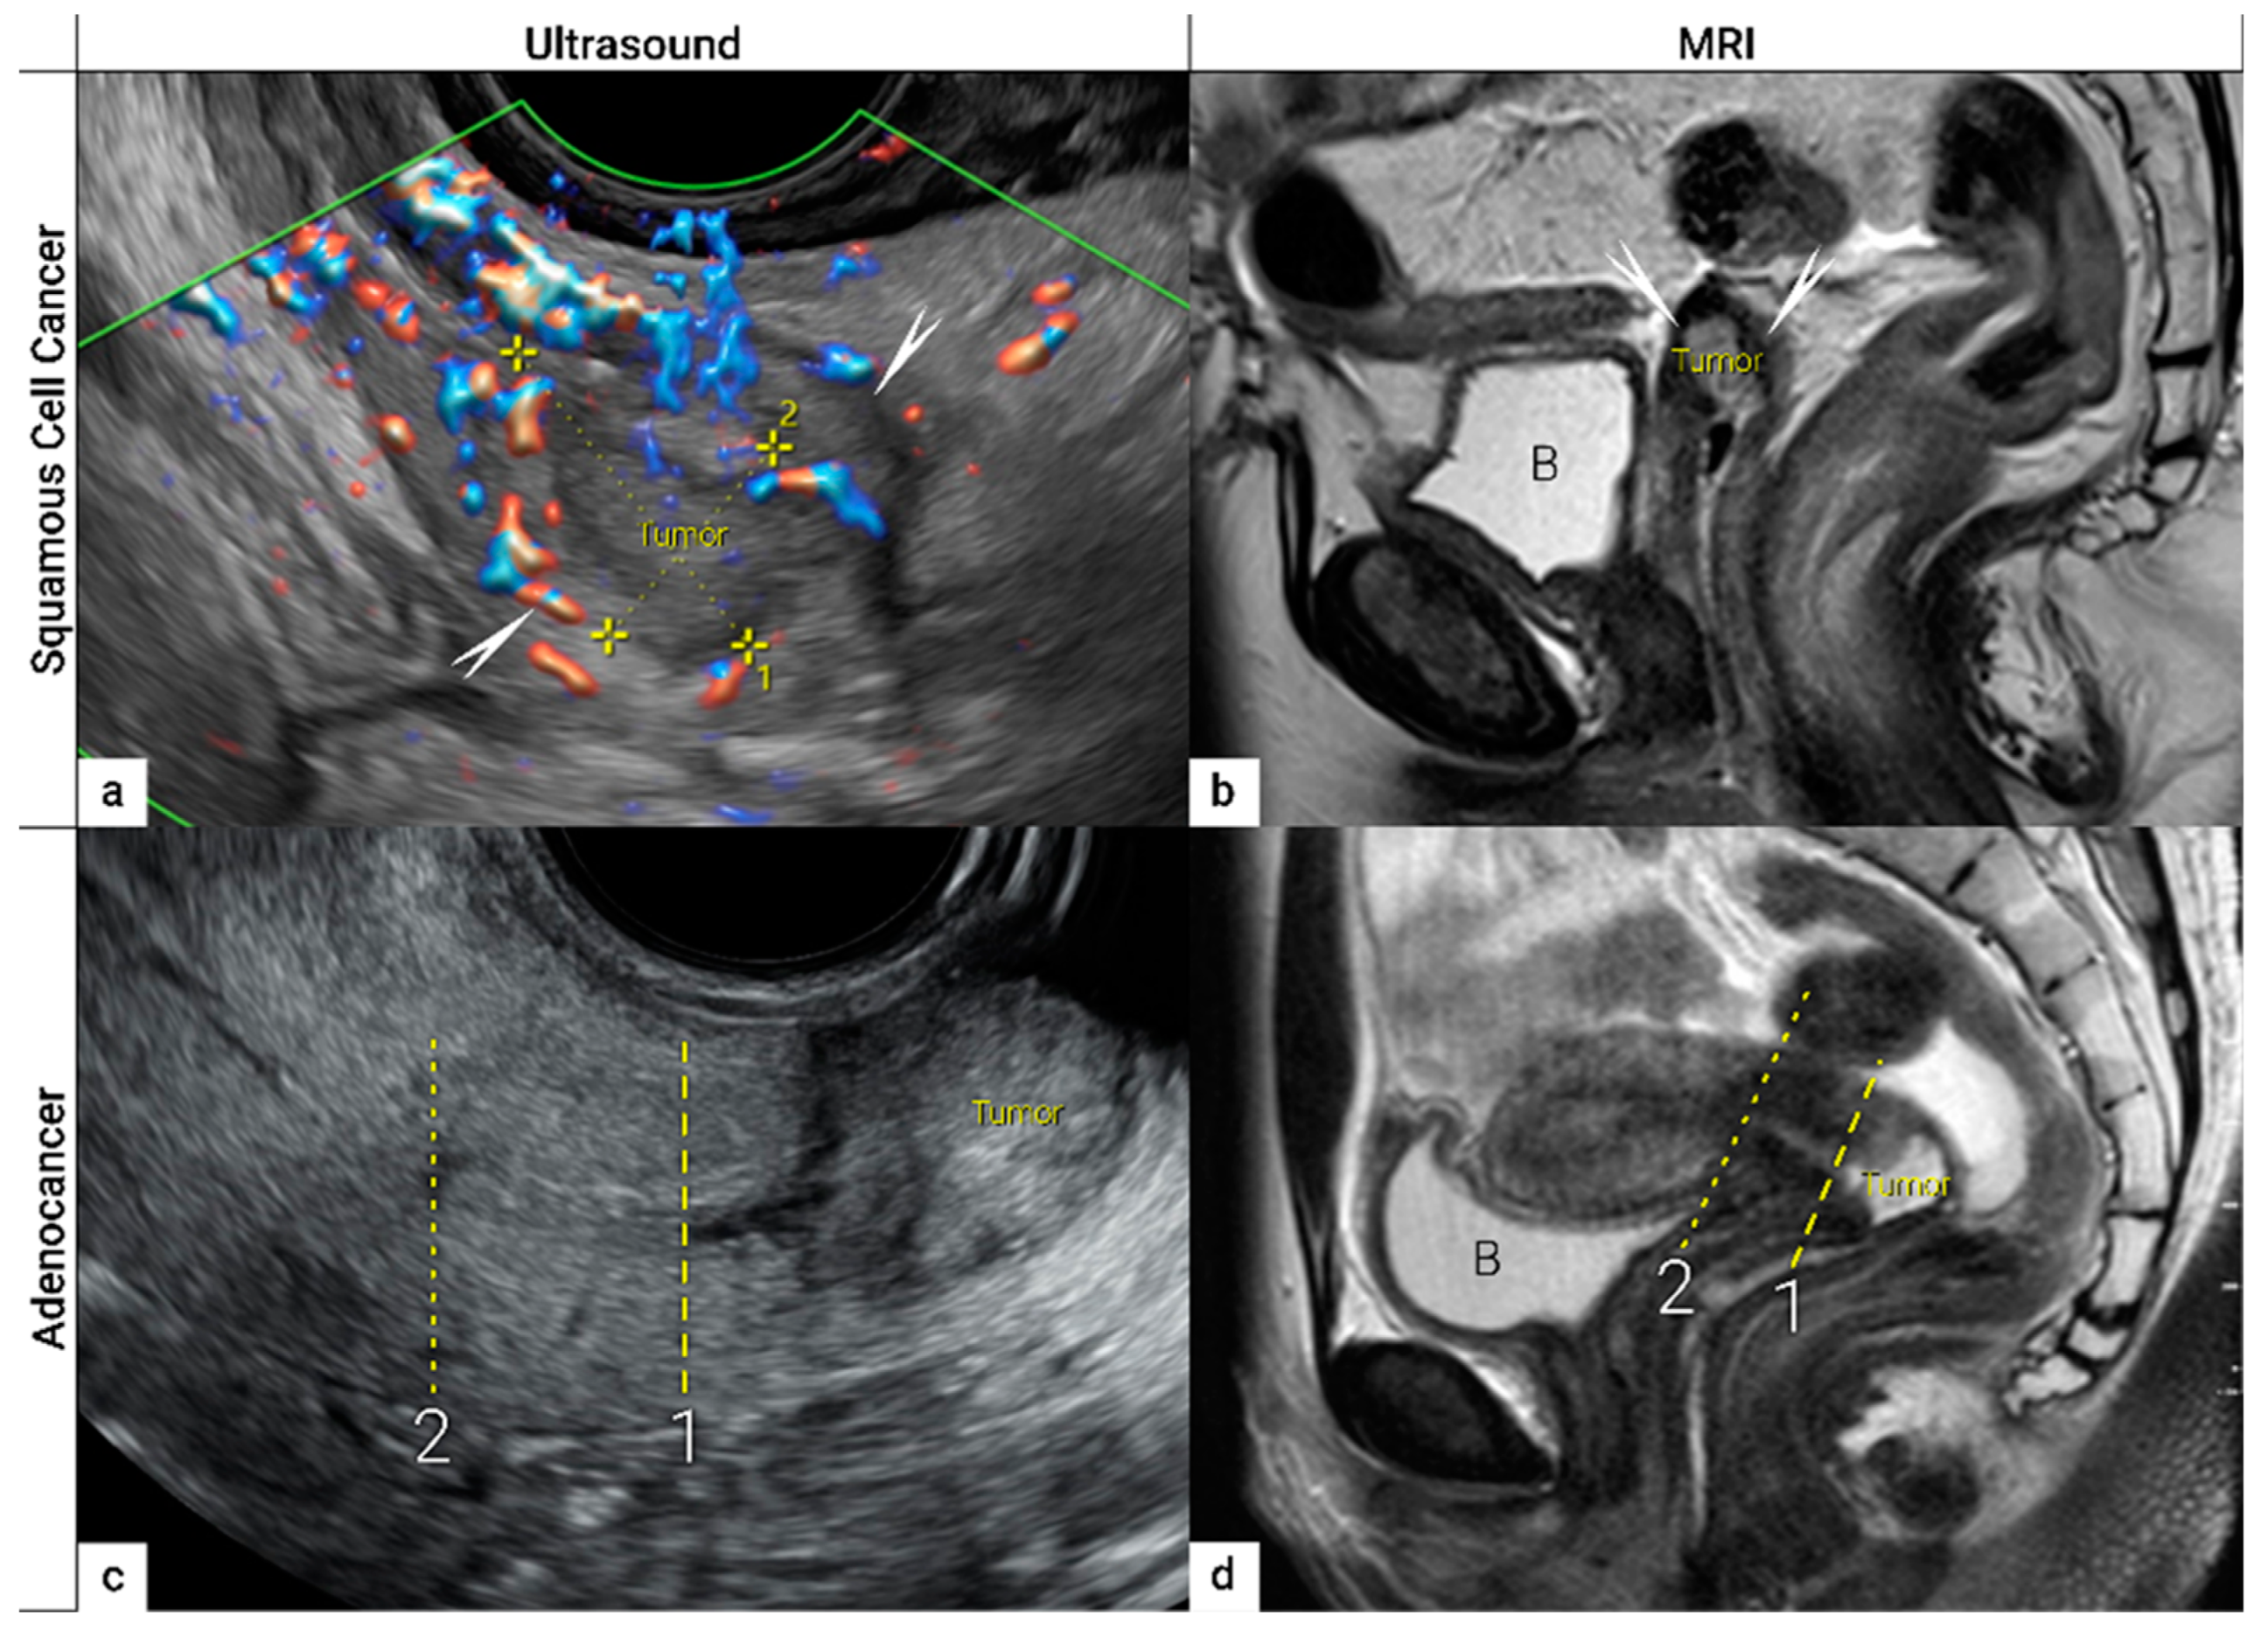

- Epstein, E.; Di Legge, A.; MÅsbäck, A.; Lindqvist, P.G.; Kannisto, P.; Testa, A.C. Sonographic characteristics of squamous cell cancer and adenocarcinoma of the uterine cervix. Ultrasound Obstet. Gynecol. 2010, 36, 512–516. [Google Scholar] [CrossRef]

| IB | Carcinoma with deepest stromal invasion >5 mm, limited to the cervix uteri with size measured by maximum tumour diameter. | US: Highly vascularised hypoechogenic (squamous-cell carcinoma) or iso-/hyperechogenic lesion (adenocarcinoma) with intact hyperechogenic pericervical fascia and positive sliding sign between tumour and bladder/rectum. MRI: Tumour has intermediate to high signal on T2W images. Dynamic CE-T1W images depicts tumour as hyperintense in the arterial phase and iso- or hypointense in the venous phase. Tumours characteristically exhibit restricted diffusion on DWI (hyperintensity on high b-value images and low intensity on the ADC maps). Tumour does not disrupt the hypointense peripheral stromal ring (best seen on T2W images). | |